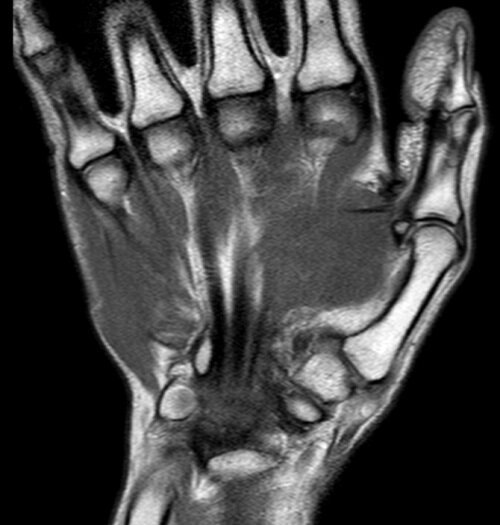

МРТ лучезапястного сустава

МРТ лучезапястного сустава является одним из приоритетных методов диагностики области соединения руки и кисти. Руки человека - это его рабочий инструмент, на который приходится самый большой процент нагрузки. А с учетом малой защищенности лучезапястный сустав - одно из самых уязвимых мест организма. И это касается не только переломов кисти, синяков и вывихов. На лучезапястный сустав приходится самое большое количество профессиональных заболеваний, связанных с монотонными сгибательно-разгибательными движениями кисти. А поскольку основной процент заболеваний лучезапястного сустава приходится не столько на костные травмы кисти, сколько на износ сухожилий, растяжение связок, ущемление нервов, то есть поражение мягких тканей,  чтобы получить подробные изображения руки, врачи предпочитают назначать МРТ.